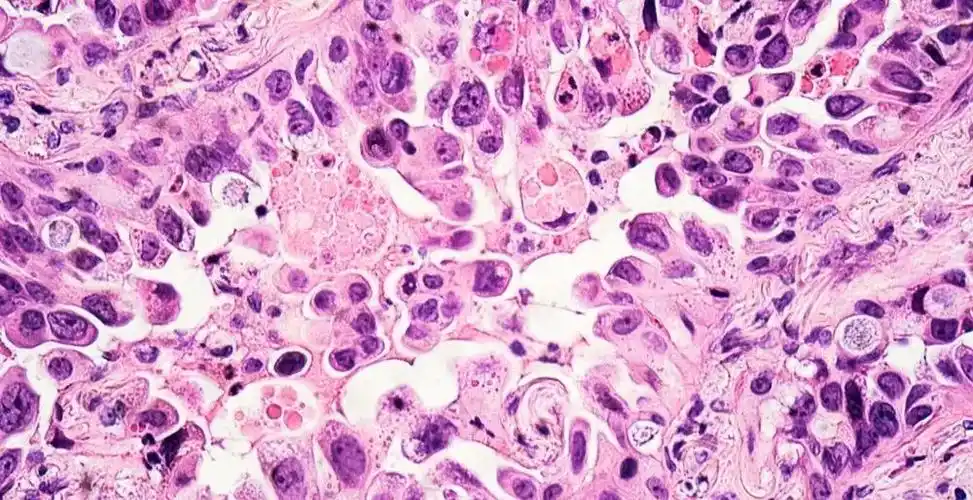

经典小细胞肺癌的病理影像分析